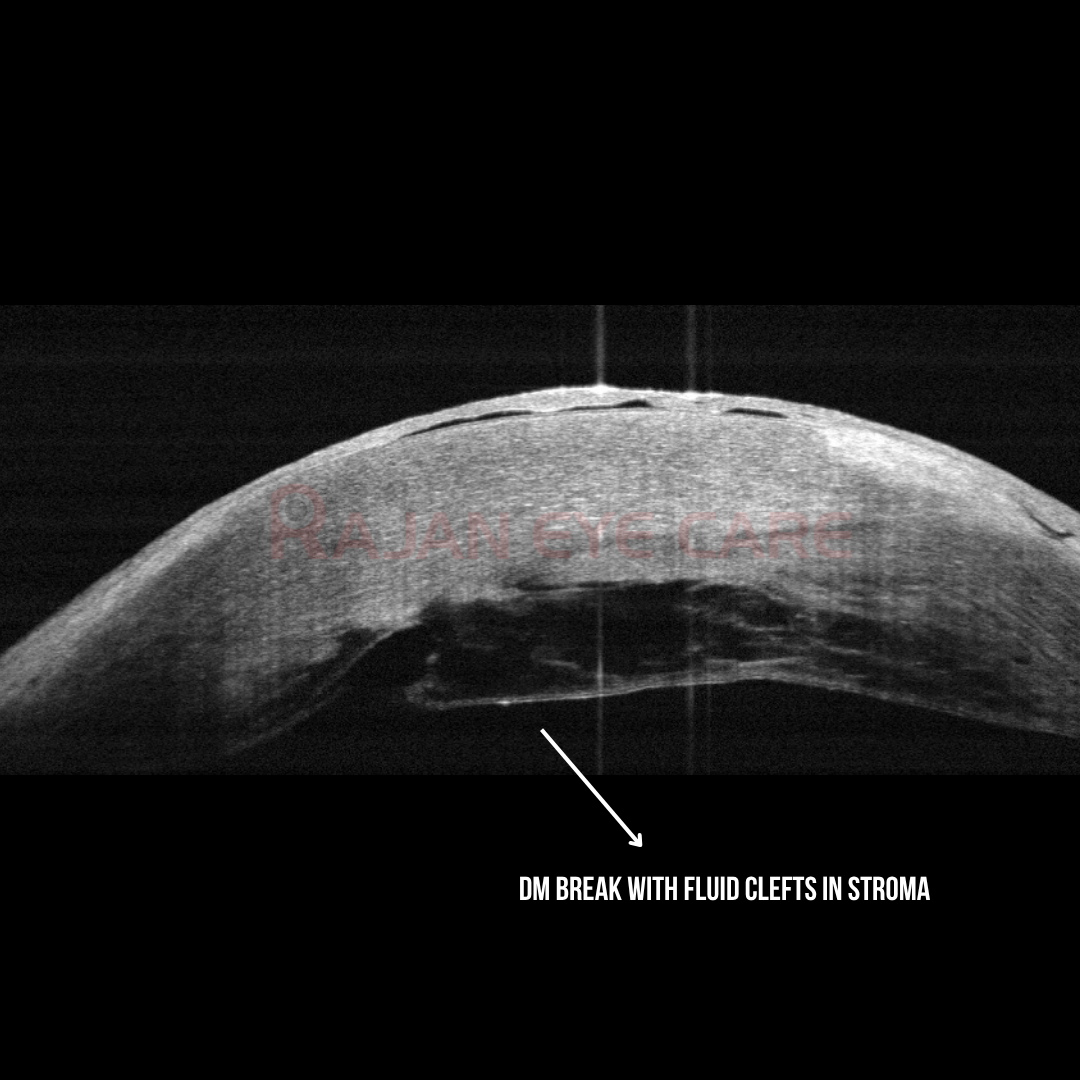

•On examination, the superior cornea showed edema, confirmed on AS OCT as acute corneal hydrops with a break in the Descemet's membrane, leading to fluid clefts in the stroma.

Hydrops: Managed Medically

A case of acute hydrops managed medically

•A 49 year old male, known case of keratoconus came with complaints of blurring of vision and redness and irritation since 1 day.

•He gave a history of eye rubbing.